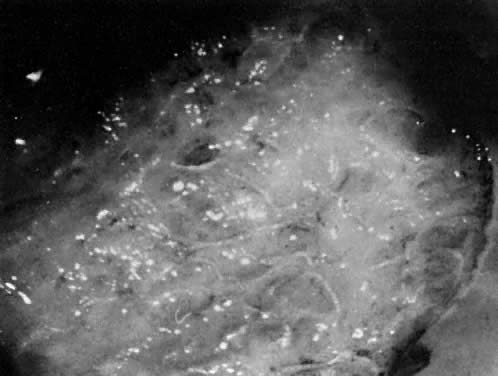

Vaginal intraepithelial neoplasia (VAIN) is the least common of the group of lower genital tract premalignancies with an annual incidence of 0.2 per 100,000 women.24 It is found most often in women who have had CIN or VIN. Its location is most often in the upper third of the vagina, and lesions are usually multifocal. The lesion can be identified by colposcopy after swabbing suspected areas of the vagina with 4% acetic acid. Lesions in the vagina may be white or flat or have a raised condylomatous pattern. Although many treatment options for VAIN are available, including cryosurgery, electrocautery, radiation therapy, and surgical excision, the use of laser therapy is an excellent option. Townsend and colleagues, in 1982, reported a success rate of 90% in a series of 52 patients treated in this manner.25

Power density of approximately 500 W/cm2 with a beam diameter of 2 mm is recommended for laser vaporization of the vagina. Laser treatments should be performed with the aid of a laser hook to help increase vaginal exposure (Fig. 24). Vaporization should be carried to a depth of 1 mm or less (Fig. 25). Wide peripheral margins should be obtained to eliminate this multifocal disease. Disease in the upper third of the vagina should be treated by vaporizing the entire upper third of the vaginal canal. If there is spread of disease from the upper third to the middle third, then the upper two thirds of the vagina should be vaporized. If VAIN involves areas in all thirds of the vagina, then the entire vagina should be vaporized. This is best done in two planned sessions. The use of superpulse laser at settings varying from 100 to 300 pulses per second with a pulse interval of 0.1 to 0.3 milliseconds is recommended. This rapid pulse with rest intervals helps preserve underlying stromal tissue and shortens healing time. There is no scar formation and no reduction in vaginal capacity. This surgery is best done with a CO2 laser coupled to a colposcope under general regional anesthesia. Following laser vaporization, postoperative discomfort is minimal, and healing of the mucous membrane is restored within 4 weeks. Because postoperative bleeding is not usually a problem after laser vaporization, there is no need for routine use of solutions such as ferric subsulfate. A more recent study by Dorsey and Baggish involving 83 cases of VAIN treated by laser only resulted in an 80% cure rate with 40% of the cases requiring more than one laser treatment.26

Fig. 24. A long-handled laser skin hook facilitates exposure of a vaginal tunnel for laser vaporization. The background vaginal vault has already been treated.

Fig. 25. Close-up view of vaginal vault seen in Figure 24. The neoplastic lesion has been vaporized to a depth of 1 mm. The char has been washed away.